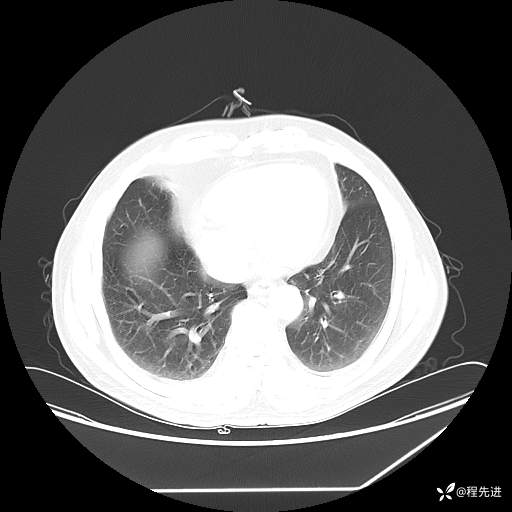

患者性别:男

患者年龄:57岁

简要病史:声嘶2月余

CT平扫+增强: